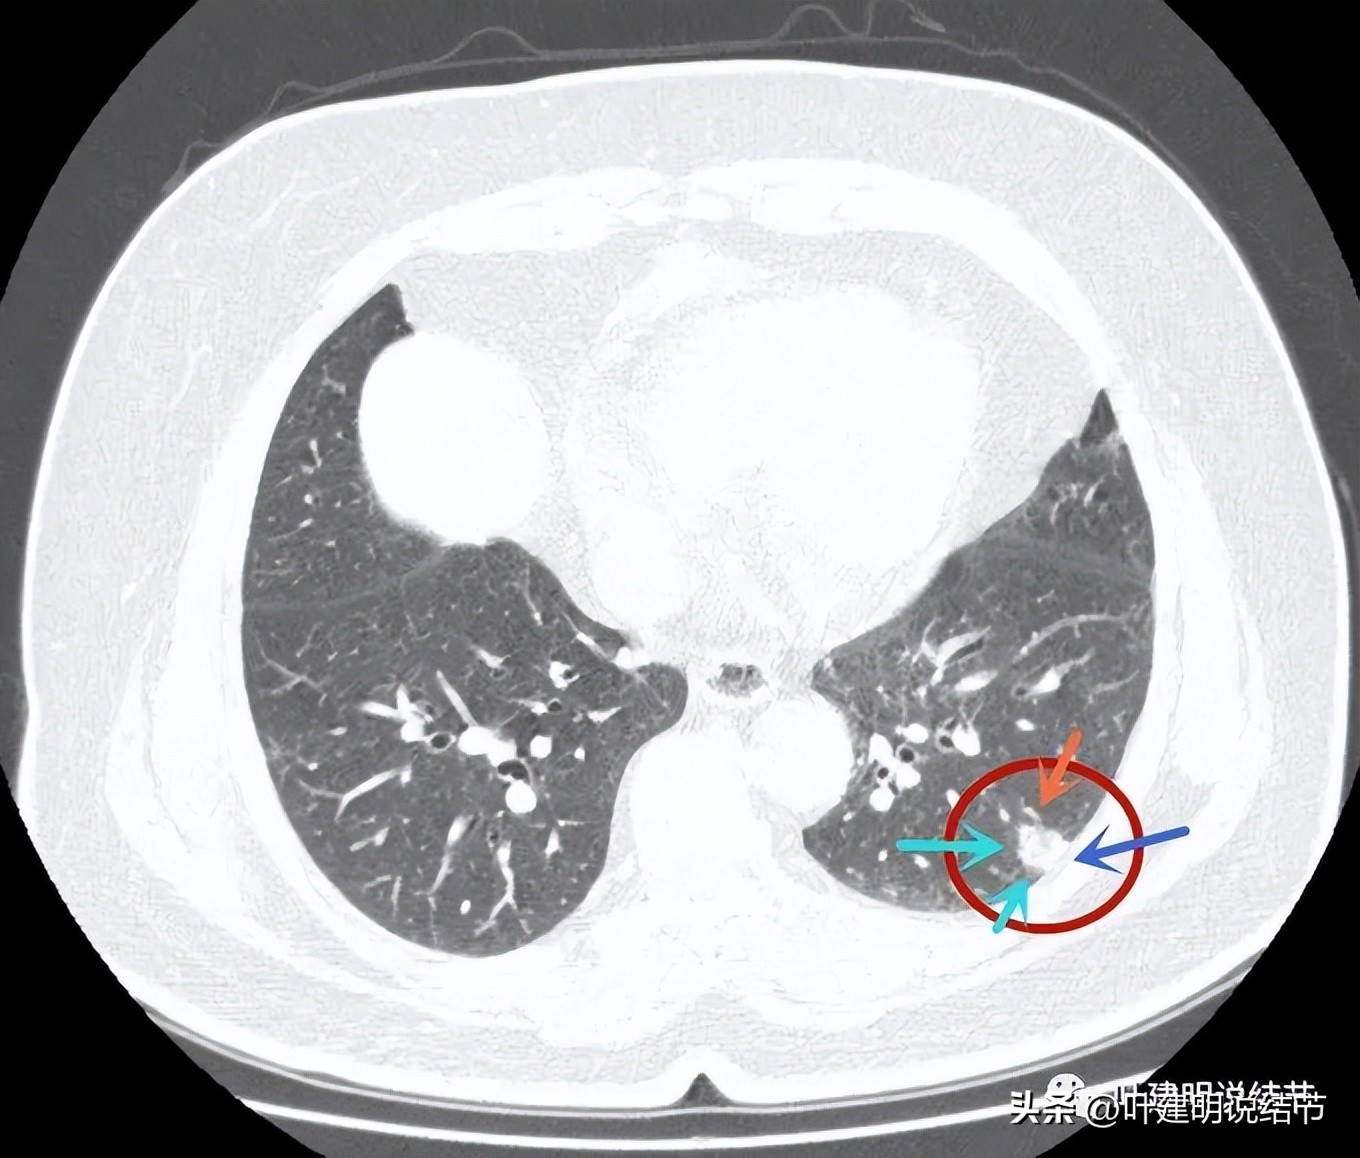

病灶近肺门侧有斑片状磨玻璃影(绿色箭头),病灶与胸壁间贴着,但没有牵拉(蓝色箭头),大部分是实性密度(粉色箭头)。

近肺门侧斑片影,胸膜距离近但没有牵拉;表面似乎有晕(砖色箭头)。

病灶不是很致密,中间有些偏低密度的成分,胸膜间隙征明显(按理这是肿瘤的特点,说明水肿不明显。但实性的,为什么没有牵拉?要么会是粘液腺癌吗?但粘液腺癌应该密度更均匀密实一些)。